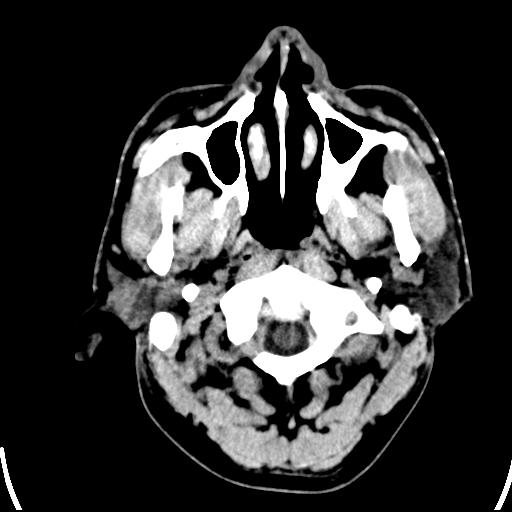

标题: CT25435:头皮下高密度影???

头皮下高密度结节影???临床上在老年男性比较常见。大家看看是什么?成因是? 本例患者,男性,51岁。外伤来诊。无染发史及发根植入史。